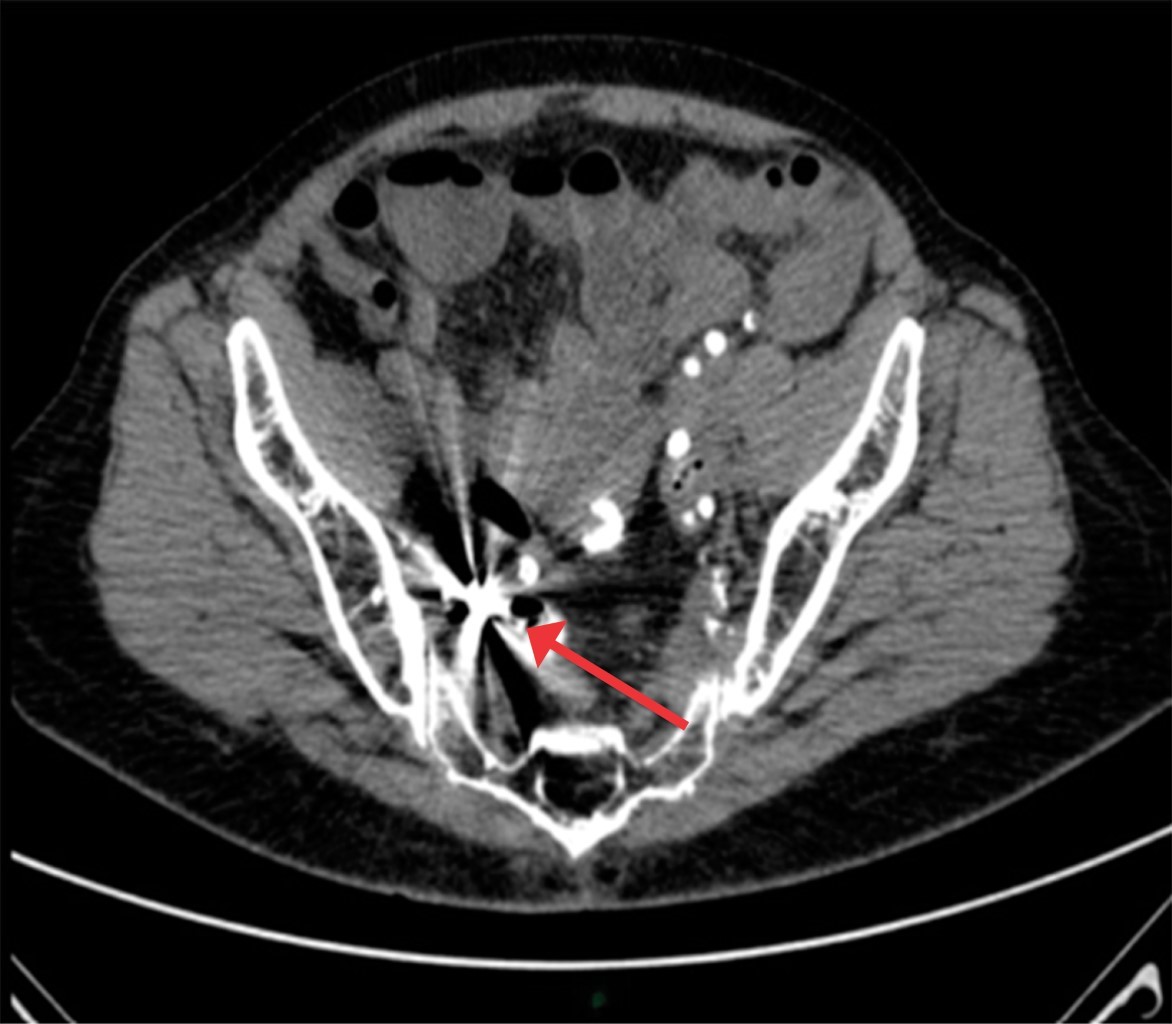

Los exámenes de laboratorio mostraron anemia normocítica normocrómica. Se realizó endoscopia y colonoscopia sin lograr encontrar una fuente clara del sangrado. Como parte de la evaluación del probable sangrado de intestino delgado, se realizó una videoendoscopia con cápsula. La CE reportó úlceras intestinales circunferenciales que causaron un sitio de estenosis donde se retuvo la cápsula. Dos semanas posteriores a la ingestión de la cápsula la paciente se presentó al Servicio de Urgencias con datos de oclusión intestinal y abdomen agudo. Los exámenes de laboratorio mostraron leucocitosis 11.1 × 103/L (4.8-11.0 × 103/L), hemoglobina de 10.2 g/dL (13.5-15.5 g/dL), así como una proteína C reactiva de 19.6 mg/dL (0.00-0.50 mg/dL). Se realizó una TAC abdominal que mostró la CE cerca del íleon terminal, además de engrosamiento ileal y de pared vesical (Figura 1).

Figura 1